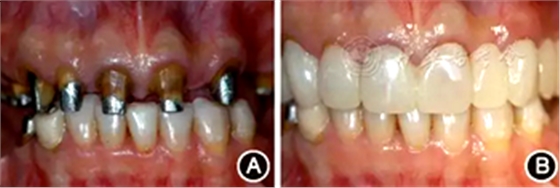

術后2周進行重新牙體預備,制作并戴入臨時修復體,牙齦塑形(圖6)。術后3個月,上前牙牙齦形、線、點位置基本穩(wěn)定,進行永久修復。上頜采用烤瓷固定橋修復,樁核冠單冠修復,下頜固定-活動義齒修復,恢復良好的牙齒外形和接觸區(qū)、重建完整牙列、恢復口腔功能、改善美學效果(圖7)。

圖6 臨時冠修復 A:牙冠延長術后2周,牙齦健康,齦緣位置及形態(tài)協(xié)調(diào);B:臨時冠修復后即刻

圖7 永久性修復后即刻 A:正面開微笑像;B:前牙像